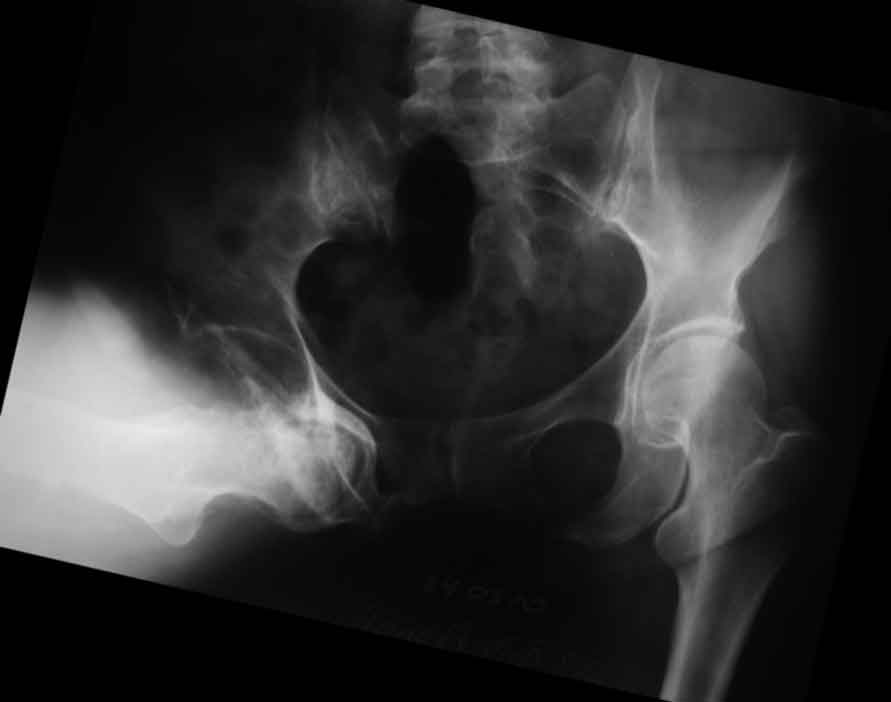

[Ortho] застарелый запирательный вывих бедра

В отделение поступила пациентка 57 лет с застарелым запирательным вывихом правого бедра.

Травма 7 лет назад, упала в лесу, местный врач вправление выполнить не смог, отправил жить

так. По разным причинам поступила для протезирования сейчас. Движения в неоартрозе есть

неплохие за исключением разгибания (с/р 120/90/0), коленный сустав с/р 140/10/0. Значимой

неврологии не определяется Планируется цементное эндопротезирование. Уважаемые

коллеги, поделитесь специфическими трудностями, с которыми сталкивались в подобных

случаях.